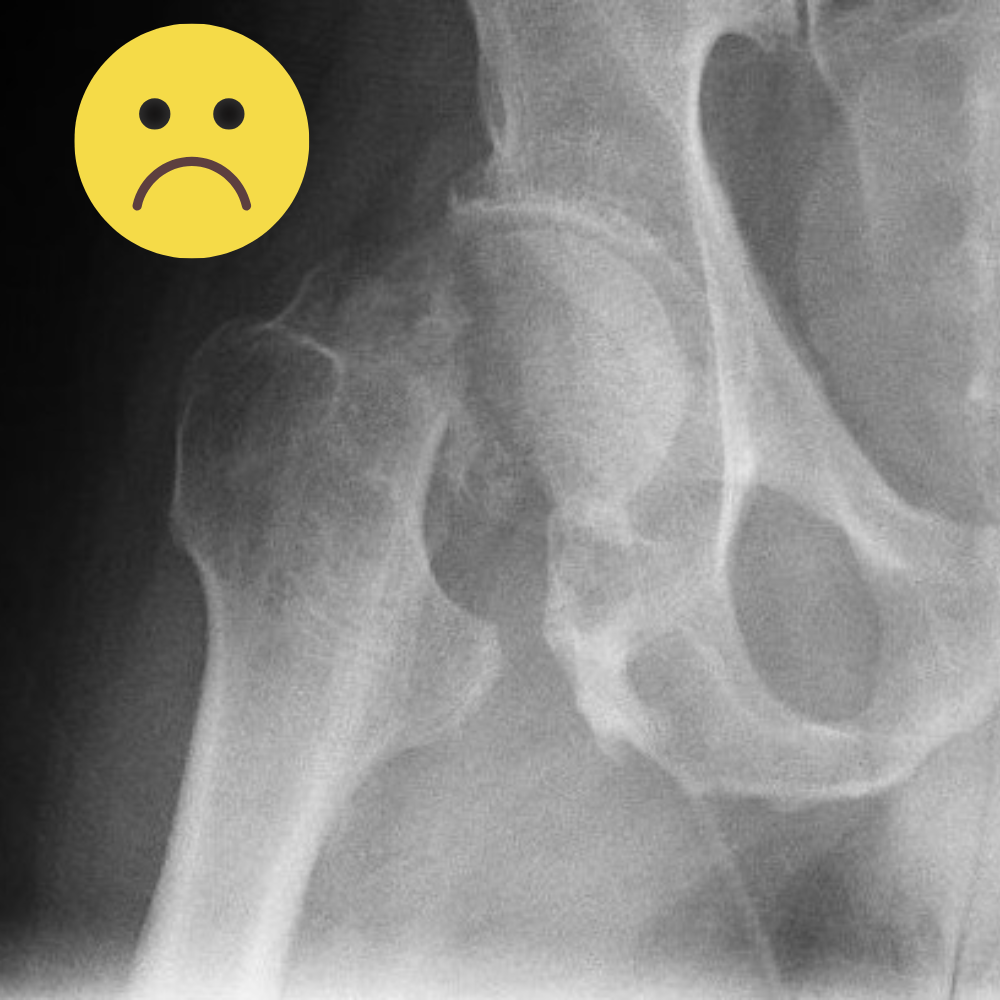

Рентгенограмма, иллюстрирующая перелом шейки бедра

У моей мамы уже два перелома шейки бедра. Врачи прямо сказали: «Коллагена-то мало, кость пустая». Не хочу повторять её путь, поэтому изучила тему вдоль и поперёк.

• реальные риски: остеопороз и тот самый перелом бедра, после которого 40 % женщин уже не возвращаются к прежней активности.